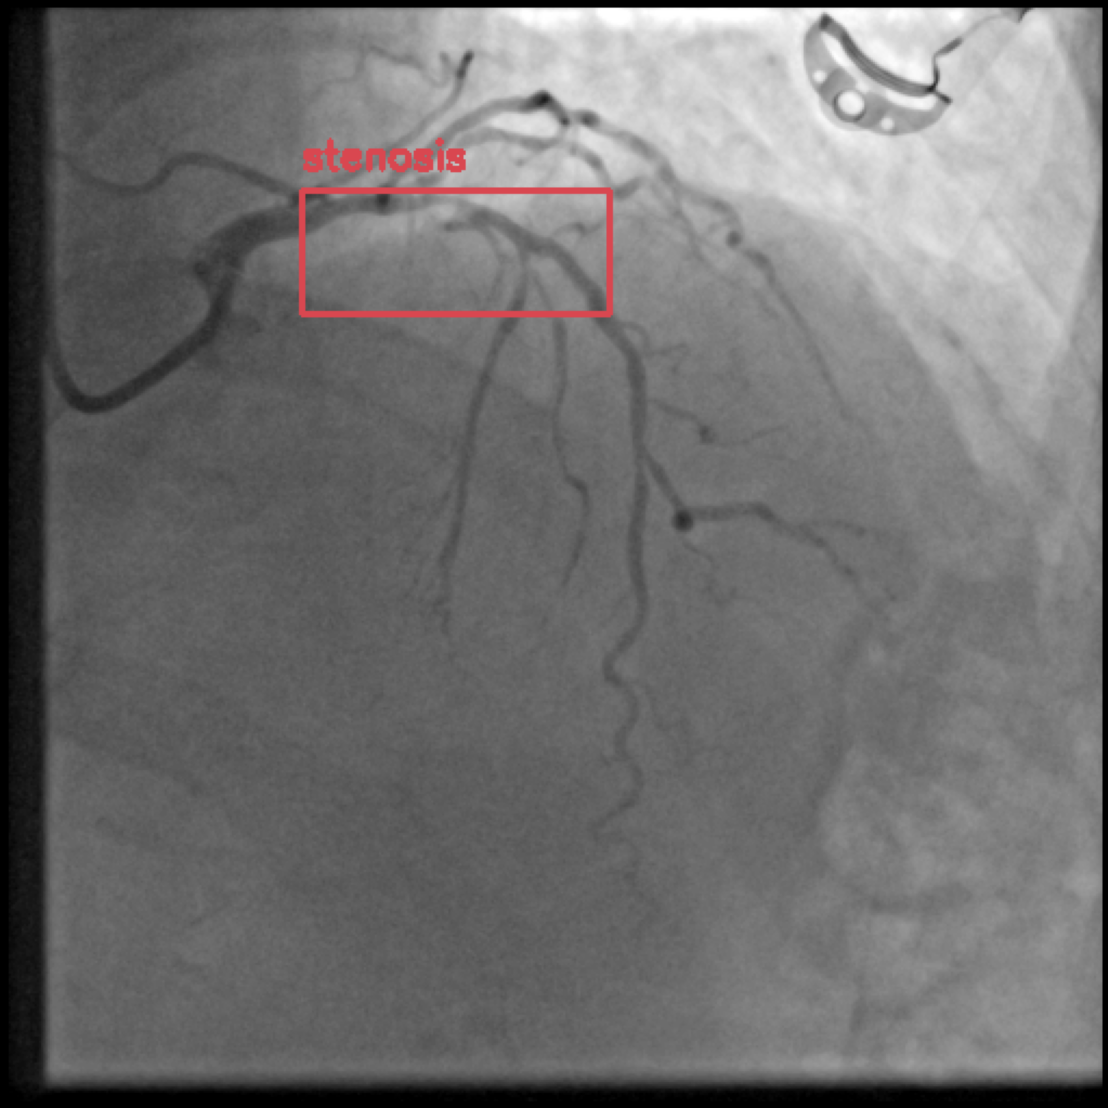

Figure 1 shows sample images from the ARCADE dataset with annotations for stenosis detection. The annotations highlight regions of arterial narrowing, providing ground truth data for training and evaluating object detection models.

To further assess the detection performance, qualitative results for three test images are presented in Figure 2. The first column shows the original images with ground truth annotations. The second, third, and fourth columns depict detections from DINO-DETR, Grounding DINO, and YOLO, respectively.

(a) Original (b) DINO-DETR (c) Grounding DINO (d) YOLO

The qualitative comparison in Figure 2 reinforces the trends observed in the quantitative evaluation. DINO-DETR produced fewer detections, occasionally missing relevant stenotic regions, consistent with its conservative detection strategy aimed at minimizing false positives [6]. Grounding DINO, although capable of identifying more regions, sometimes resulted in cluttered predictions due to over-detections [7]. YOLO provided a reasonable trade-off by effectively capturing anatomical structures while maintaining relatively high confidence scores and clear visualizations [5].